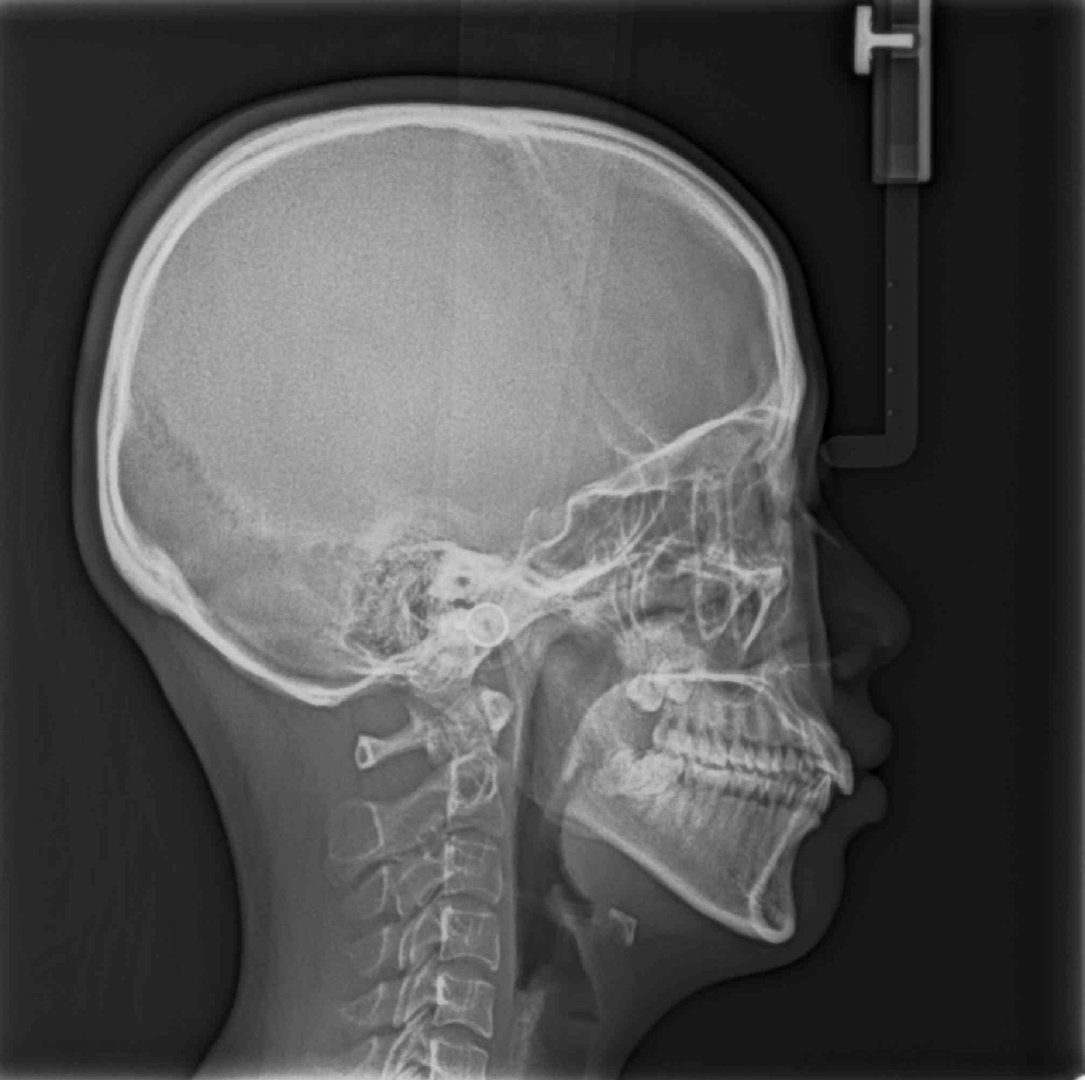

这张侧位片必不可少哦,大家看她是骨性偏多还是牙性偏多呢?

最靠谱的方法是去面诊医生,医生根据临床检查、模型分析、X线头影测量来鉴别诊断是骨性偏多,还是牙性偏多。